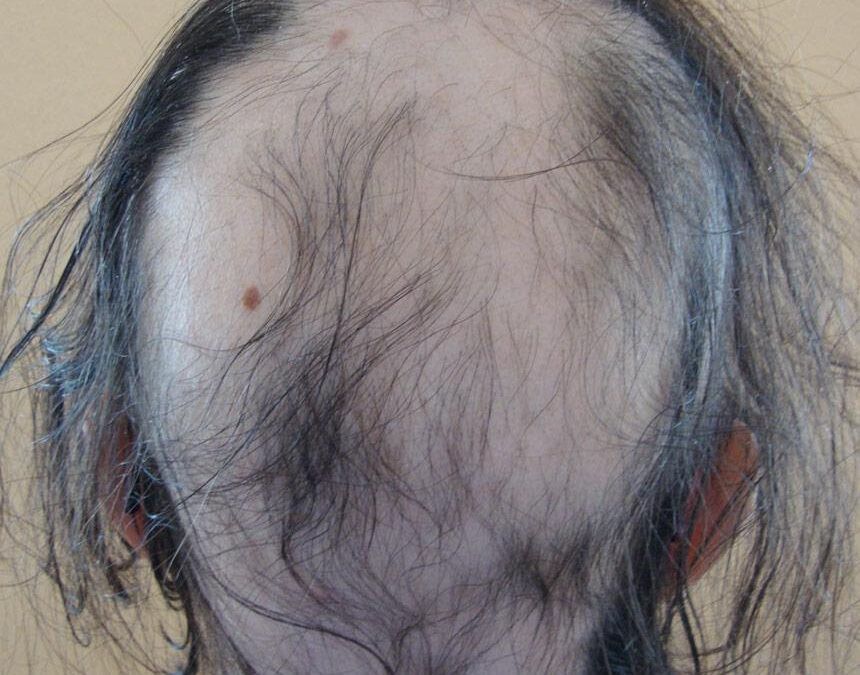

ALOPECIA AREATA La Alopecia areata es una enfermedad autoinmune en la que el sistema inmunológico ataca los folículos pilosos, causando pérdida de cabello en áreas localizadas. ¿CÓMO SE PRESENTA? La forma clásica es: Placas redondas u ovaladas sin cabello Piel...